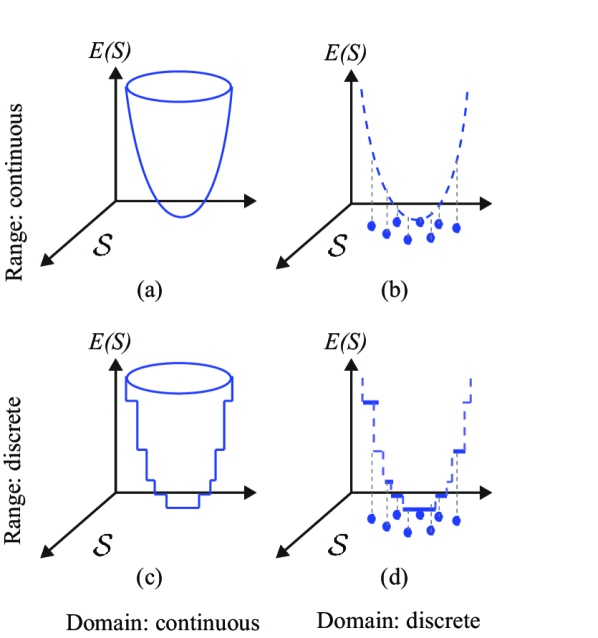

The energy function describing a segmentation problem can also be formulated in a discrete or continuous domain. Depending on the solution space (discrete vs. continuous) and the energy values, four possible cases can be considered for an energy functional (Figure 2). In the spatially discrete setting, the energy function is defined over a set of finite variables (nodes and edges), leading to the adoption of graphical models (Wang et al., 2013). One of the most commonly used graphical models is the Markov random field (MRF) (Wang et al., 2013). In MRF formulations, solutions are often calculated using graph cut methods, e.g. max-flow/min-cut algorithms or graph partitioning methods. Conversely, in the spatially continuous setting, energy functionals are continuous and so are the optimality conditions, which are written in terms of a set of partial differential equations (PDE). The minimization problem in (3) is a continuous version of a multi-region segmentation functional, often called minimal partition problem in the PDE community (Nieuwenhuis et al., 2013). Note that in Figure 2, the objective function is a cost or an energy function that has to be minimized. Nevertheless, an objective function can also be a fitness or utility function that has to be maximized.